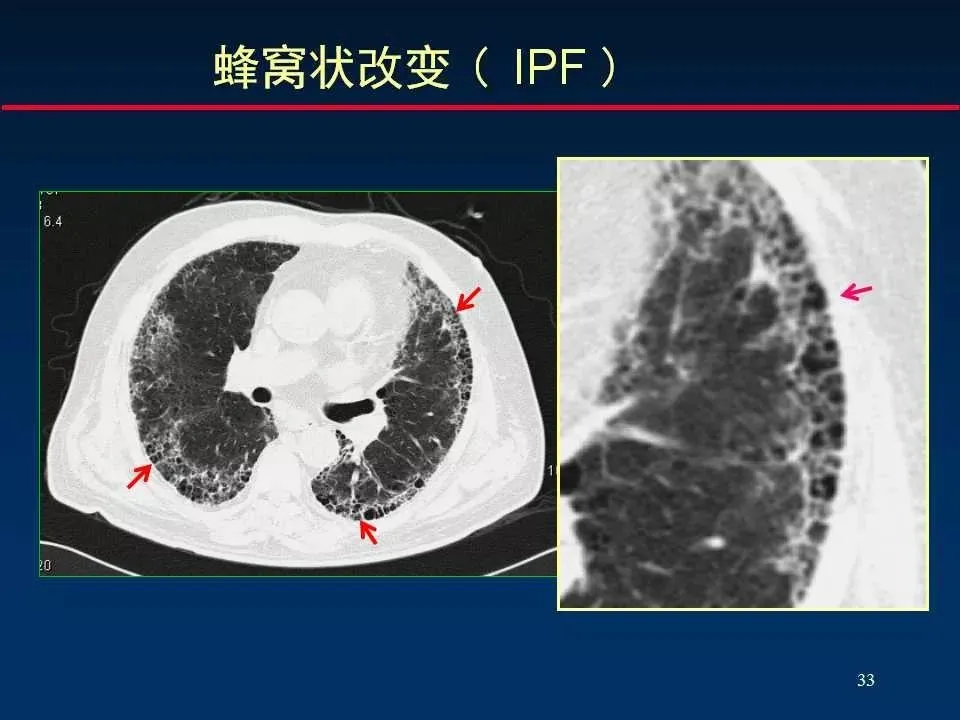

5、蜂窝状改变 Honeycombing opacity